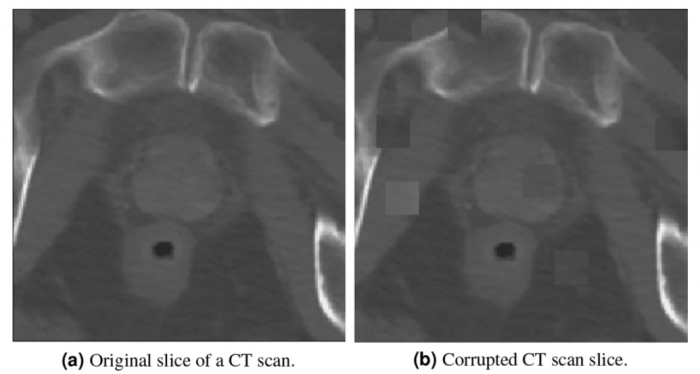

這方面的最新例子來自皇家墨爾本理工大學和圣文森特醫院的研究人員,他們從患有和未患有前列腺癌的無癥狀患者的CT掃描開始。科學家們指出,一般來說,CT掃描對檢測骨骼和關節問題等疾病很有用,但放射科醫生很難用它們來檢測前列腺癌。

利用CT掃描,人工智能軟件被訓練來搜索可能表明該疾病的不規則現象。該工具隨著每次掃描的進行而改進,完善其能力并適應分析不同機器的掃描,最終發現疾病的最小特征。隨著時間的推移,它能夠勝過放射科醫生,在幾秒鐘內檢測出癌癥的生長,甚至在病人出現任何癥狀之前。